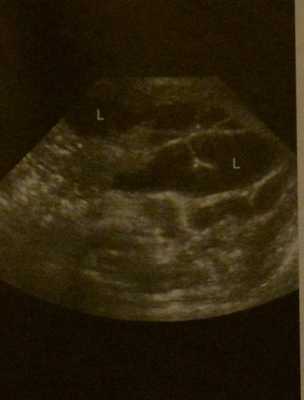

Лимфангиома у новорожденного. УЗИ. Крупная кистозная лимфангиома шеи справа (L )Типичная ультразвуковая морфология: мультикистозное образование с множеством перегородок и отсутствием сигнала потока при цветном допплеровском УЗИ.